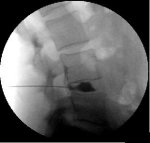

How is Discography performed?

The procedure is done in a surgical center with fluoroscopic (x-ray) guidance. For lumbar discography it is done with you lying on your stomach. You will be given intravenous sedation to help you be comfortable and relaxed. You are watched closely with an EKG monitor, blood pressure cuff and blood oxygen-monitoring device. The skin over the injection site(s) is cleaned with an antiseptic solution and then the injections are performed.